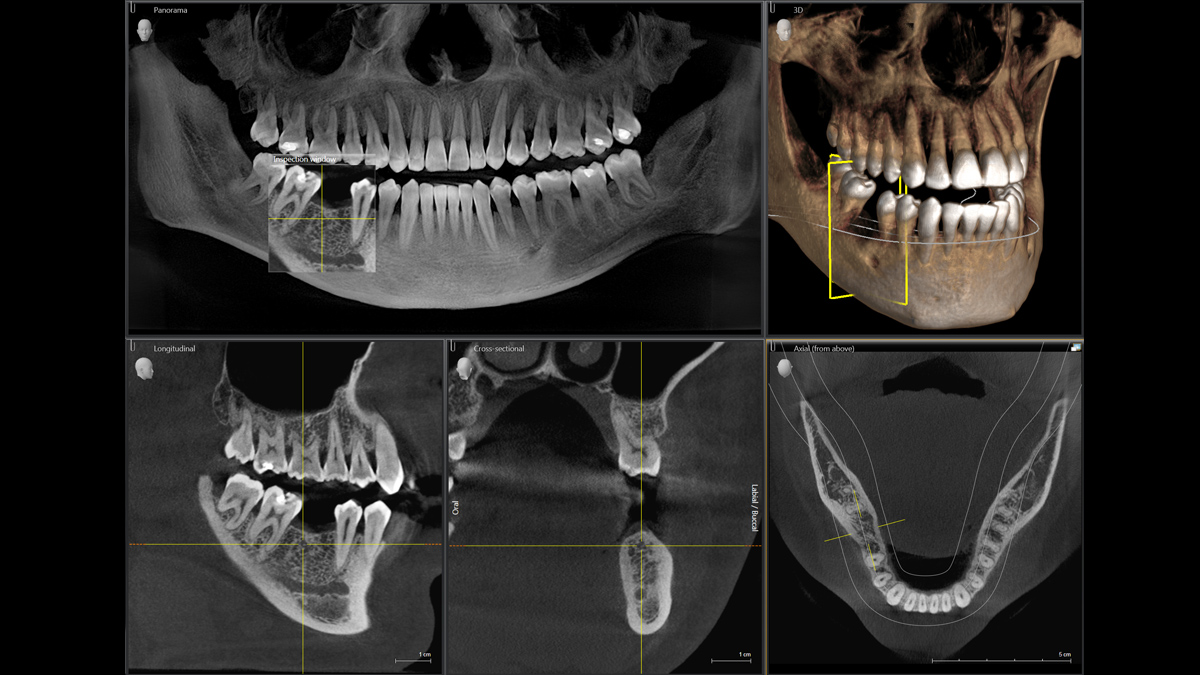

La tecnología 3D se está estableciendo cada vez más en los consultorios dentales en todo el mundo. Para diagnósticos más precisos y explicaciones del tratamiento, los rayos X en 3D ofrecen varias ventajas. Ya sea para dientes superpuestos, recorridos inesperados de los canales de los nervios, raíces ocultas o anomalías de las articulaciones temporomandibulares, las imágenes en 3D tienen un valor inestimable para un gran número de diagnósticos.

Orthophos SL 3D ofrece una gran variedad de opciones para satisfacer estas necesidades: diferentes tamaños de volumen donde elegir, modos HD/SD/Dosis bajas de radiación y un software inteligente e intuitivo para aprovechar al máximo las imágenes obtenidas y vincularlas directamente al tratamiento.

Galería de muestra de imágenes panorámicas 3D

Orthophos SL 3D en la práctica